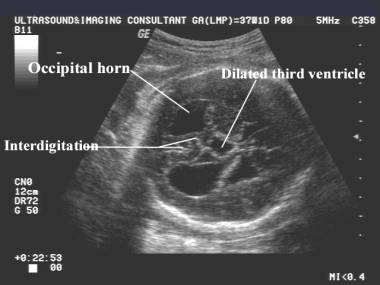

Colpocephaly |

Colpocephaly (dilatation of the occipital horn of the

lateral ventricle). |

o

Absence

of the cavum septi pellucidi, upward displacement and enlargement of the third

ventricle

Enlarged

occipital horns (colpocephaly) of the lateral ventricles,

separated

and enlarged anterior horns,

interhemispheric spaces are the key indirect signs of CACC.